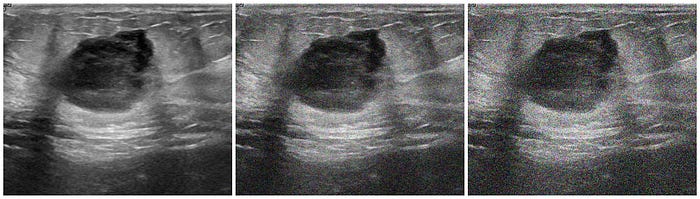

In the context of medical image augmentation, "shadowing" refers to the simulated appearance of shadows or shading effects within an image. It's an augmentation technique that aims to introduce variations similar to what might be observed in real-world medical images due to lighting conditions or tissue properties.

This paper by R. Singla et al. points out the acoustic shadowing as "one of the most often encountered artifacts in ultrasound." According to the paper, shadows in an image may be caused by insufficient contact between the transducer and the surface or locations with large acoustic impedance variations between tissue interfaces.

One downside is that most acoustic shadows are and should be manually segmented due to the fact that areas of focus may be different for each image. I won't be going over the code in this article, but it is important to note that some sort of shadowing or "black-out" technique is useful for medical image augmentation.